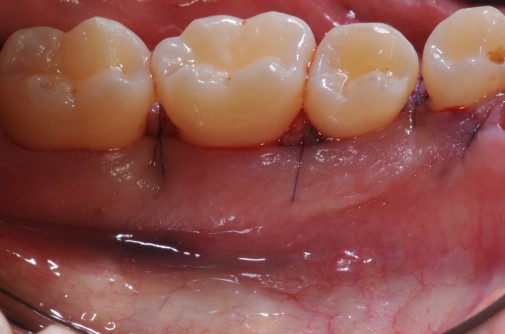

Radiographic view before periodontal regenerative therapy with Straumann® Emdogain®. A deep intrabony defect appeared mesially and distally on the left mandibular first premolar. Pre-surgical probing measured 8 mm. The defect morphology presented as well-contained.